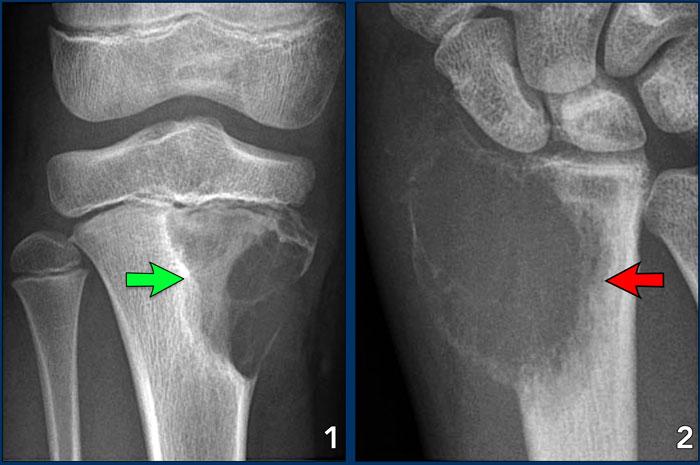

Images

- U sợi sụn nhầy

Một tổn thương lành tính, giới hạn rõ, dạng giãn nở với sự phá hủy vỏ xương có quy tắc và một lớp xương mới ở ngoại vi. - U tế bào khổng lồ

Tổn thương xâm lấn tại chỗ với phá hủy vỏ xương, giãn rộng và một lớp xương mới mỏng, gián đoạn ở ngoại vi.

Lưu ý vùng chuyển tiếp rộng về phía khoang tủy, đây là dấu hiệu của hành vi xâm lấn (mũi tên đỏ).